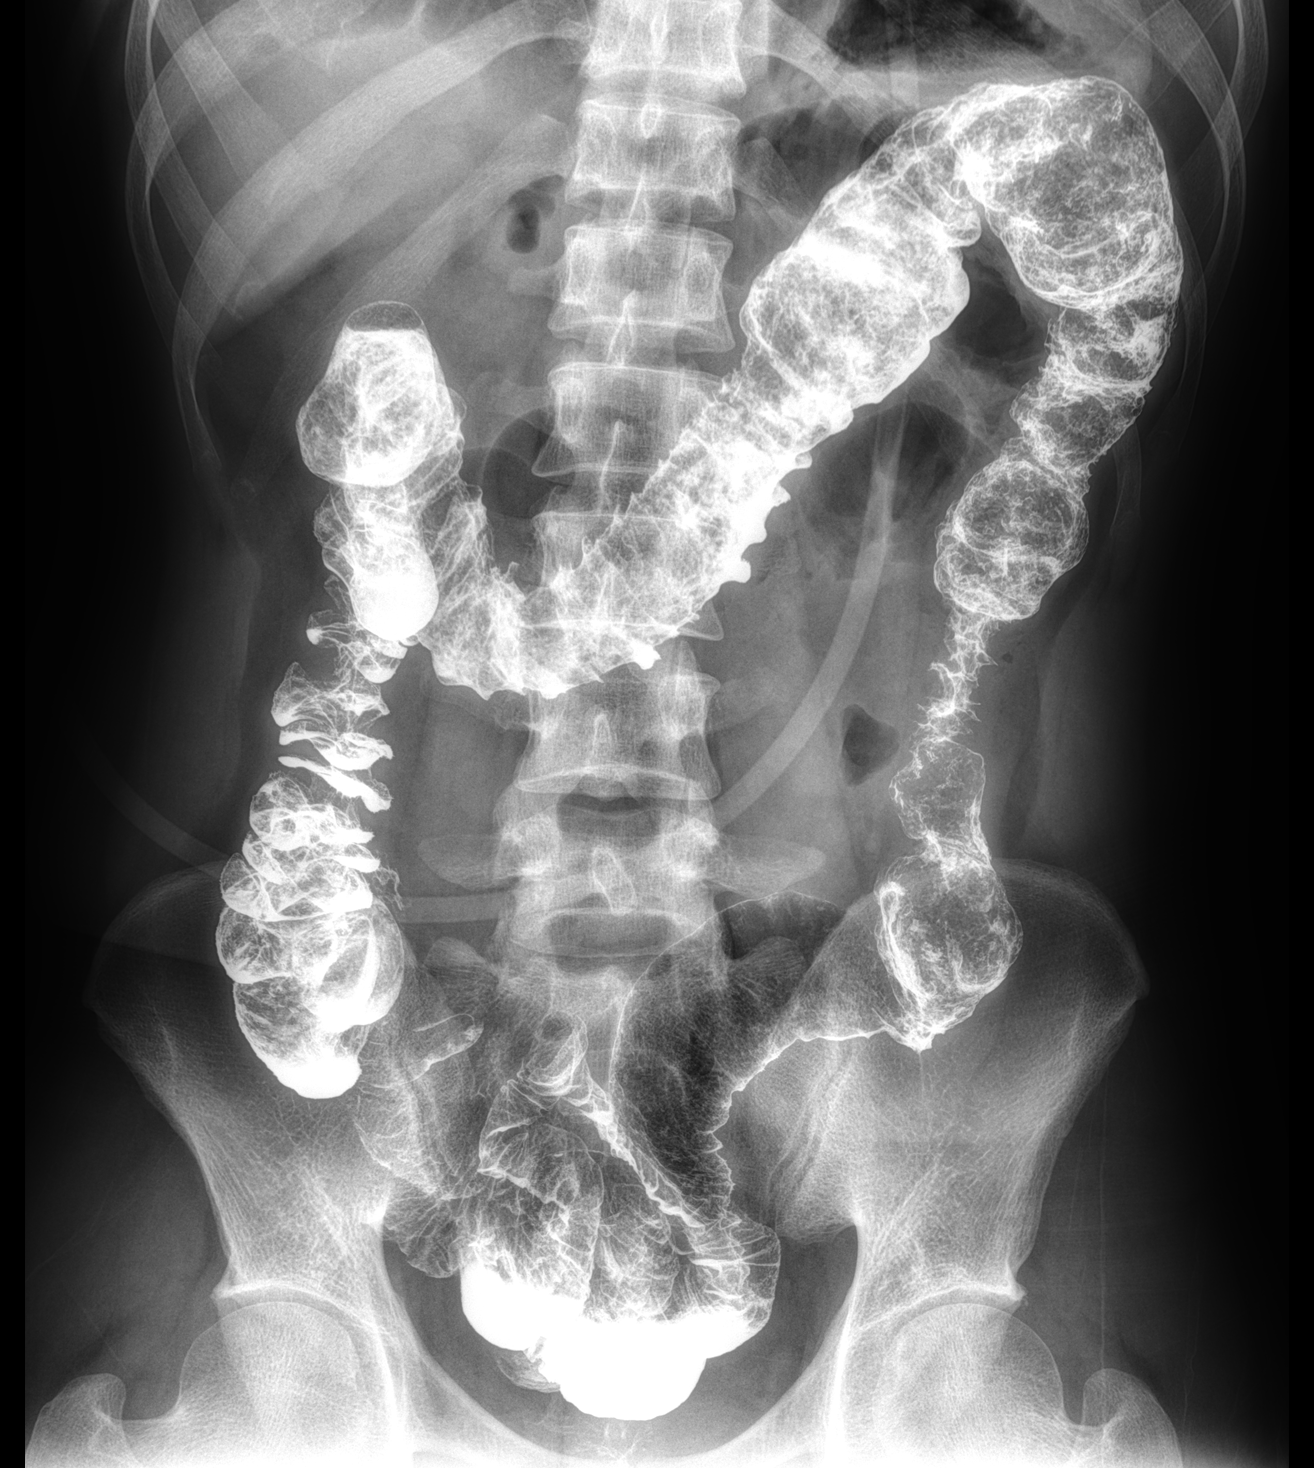

平板探测器

超大尺寸

超范围

超高像素

高清点片